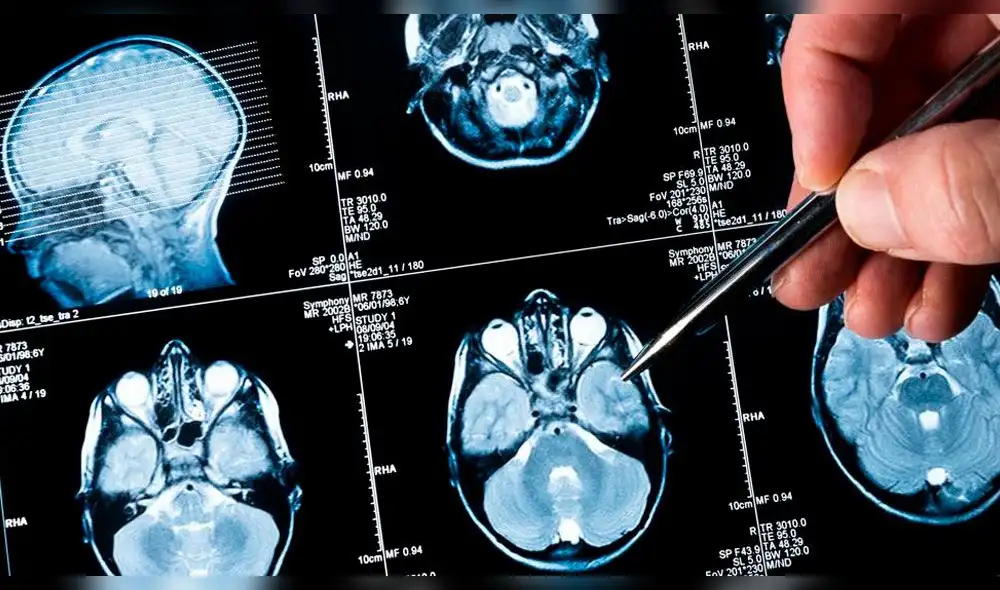

Niña salva de morir luego de que tumor cerebral que tenía desapareció inexplicablemente